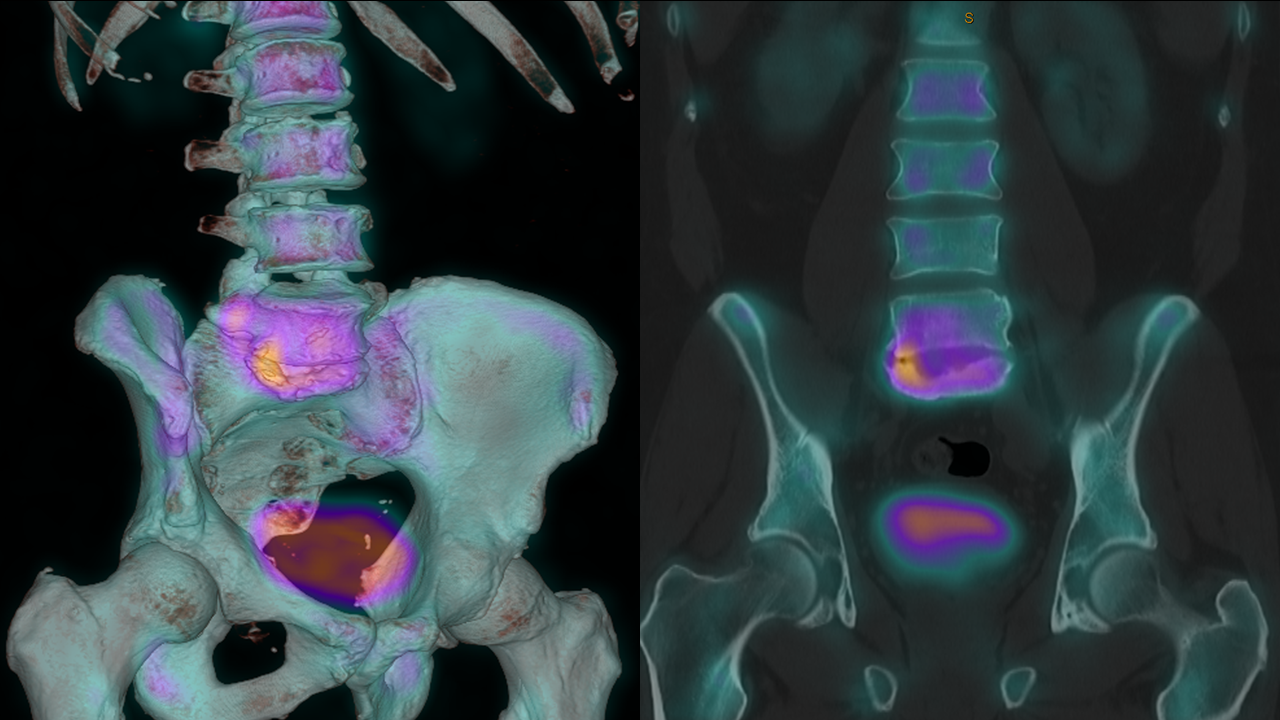

Color-enhanced medical scans showing the human pelvis, lower spine, and hips from two different angles.